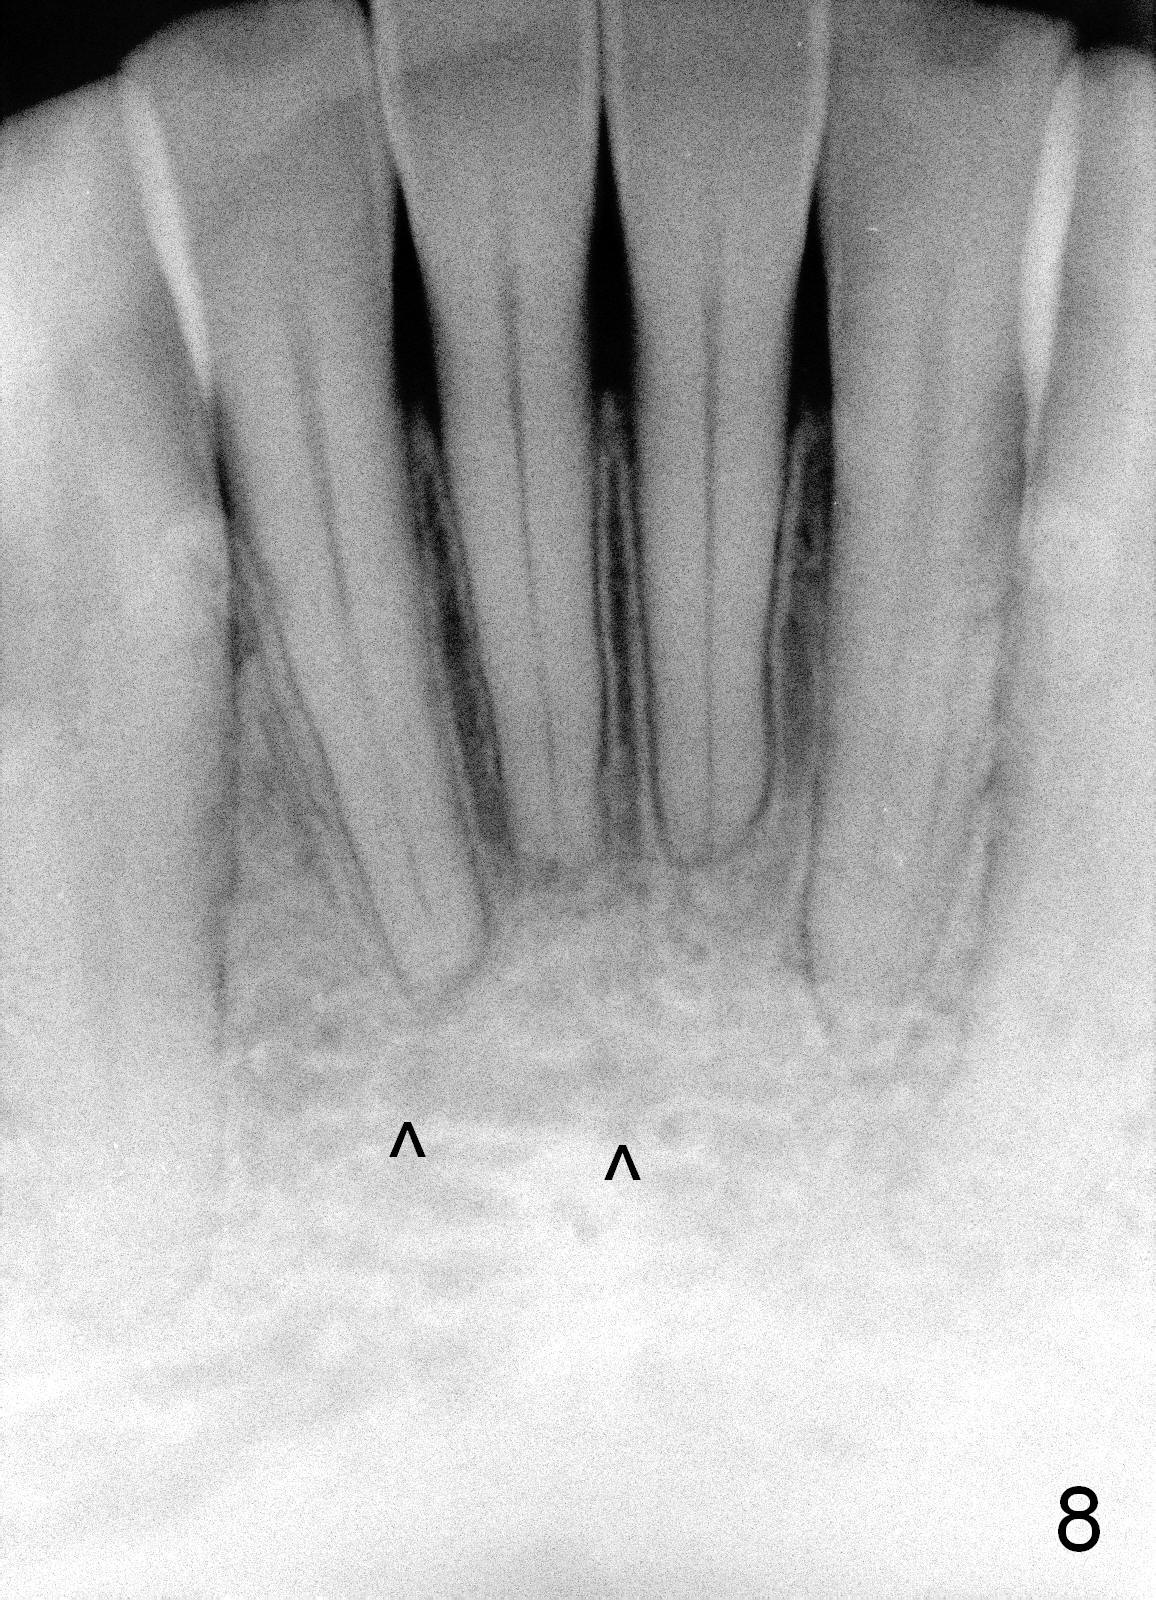

To correct the gingival margin associated with #8 implant, bone graft is needed.  Particulate graft may not stay in place. Chin graft is harvested.  Since the roots of the lower anterior teeth are long (Fig.8), the width of the chin graft is limited for direct screw fixation (Fig.9,10).  Titanium mesh is used for fixation of the graft.  Connective tissue graft from the palate is to increase bulk at the site of #8 (Fig.11 *).  There is no symptom or sign of infection 1 month postop (Fig.12,13).  Although there is alteration of sensation of the lower incisors, there is no apical radiolucency of them 4 months postop (Fig14).  There is no abnormality associated with the bone graft and Titanium mesh (Fig.15).